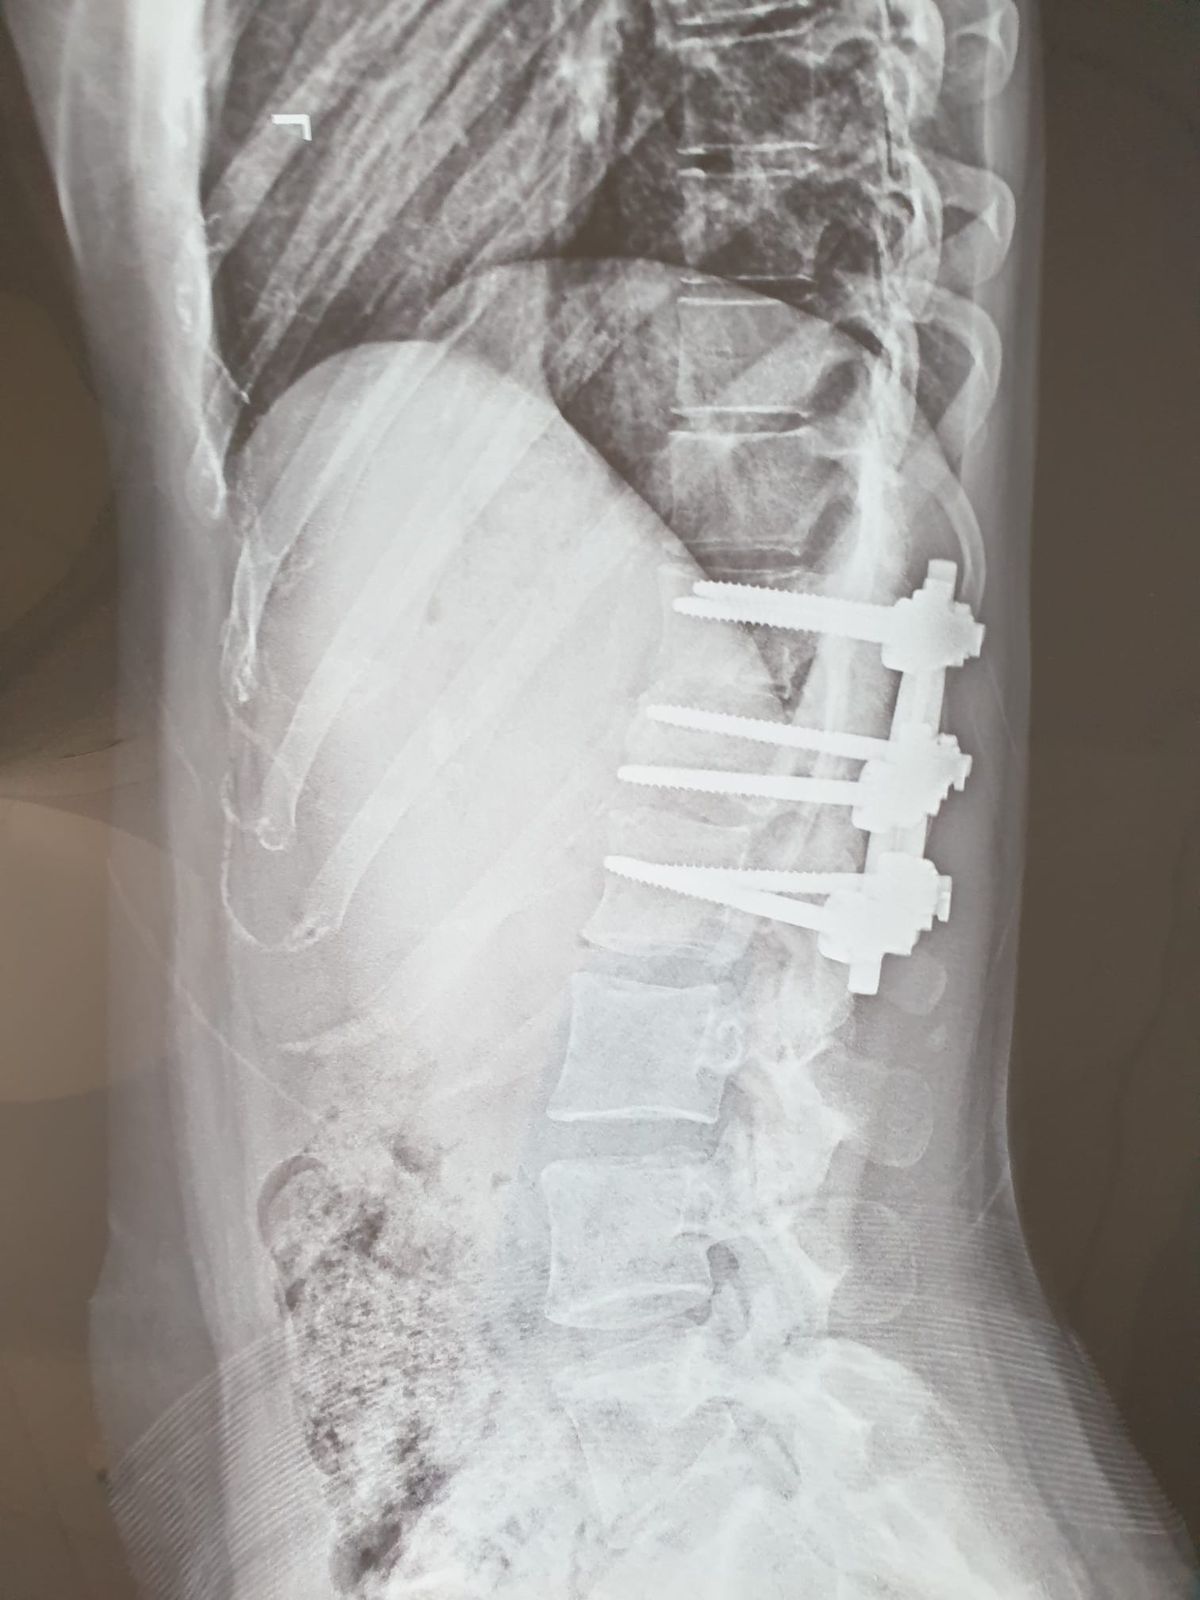

Foto 4/40